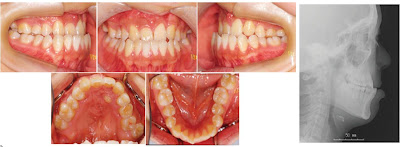

Este artigo descreve o tratamento ortodôntico cirúrgico da hipoplasia maxilar em um paciente com fissura de lábio e palato com distração osteogênica da maxila com distratores maxilares interno.

O avanço da maxila foi realizado para corrigir o perfil facial e a retrusão maxilar numa má oclusão de Classe III. O movimento de rotação do segmento da distração foi feito para corrigir a parte superior da linha média dentária.

Embora o avanço da maxila tenha sido insuficiente por causa do rompimento inesperado do distrator intra-oral após a conclusão da distração, a tração esquelética com uma máscara facial compensou a escassez. A melhora estética foi bem sucedida e a estabilidade oclusal pós-tratamento foram alcançados sem recidiva perceptível após dois anos de contenção.